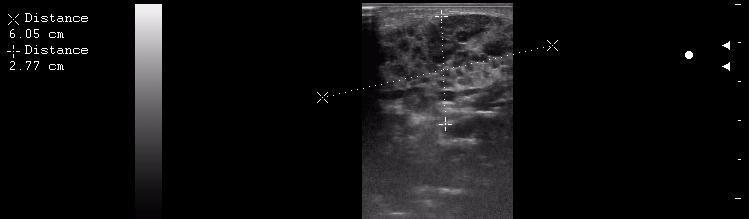

интранодулярные лимфоузлы в околоушной железе